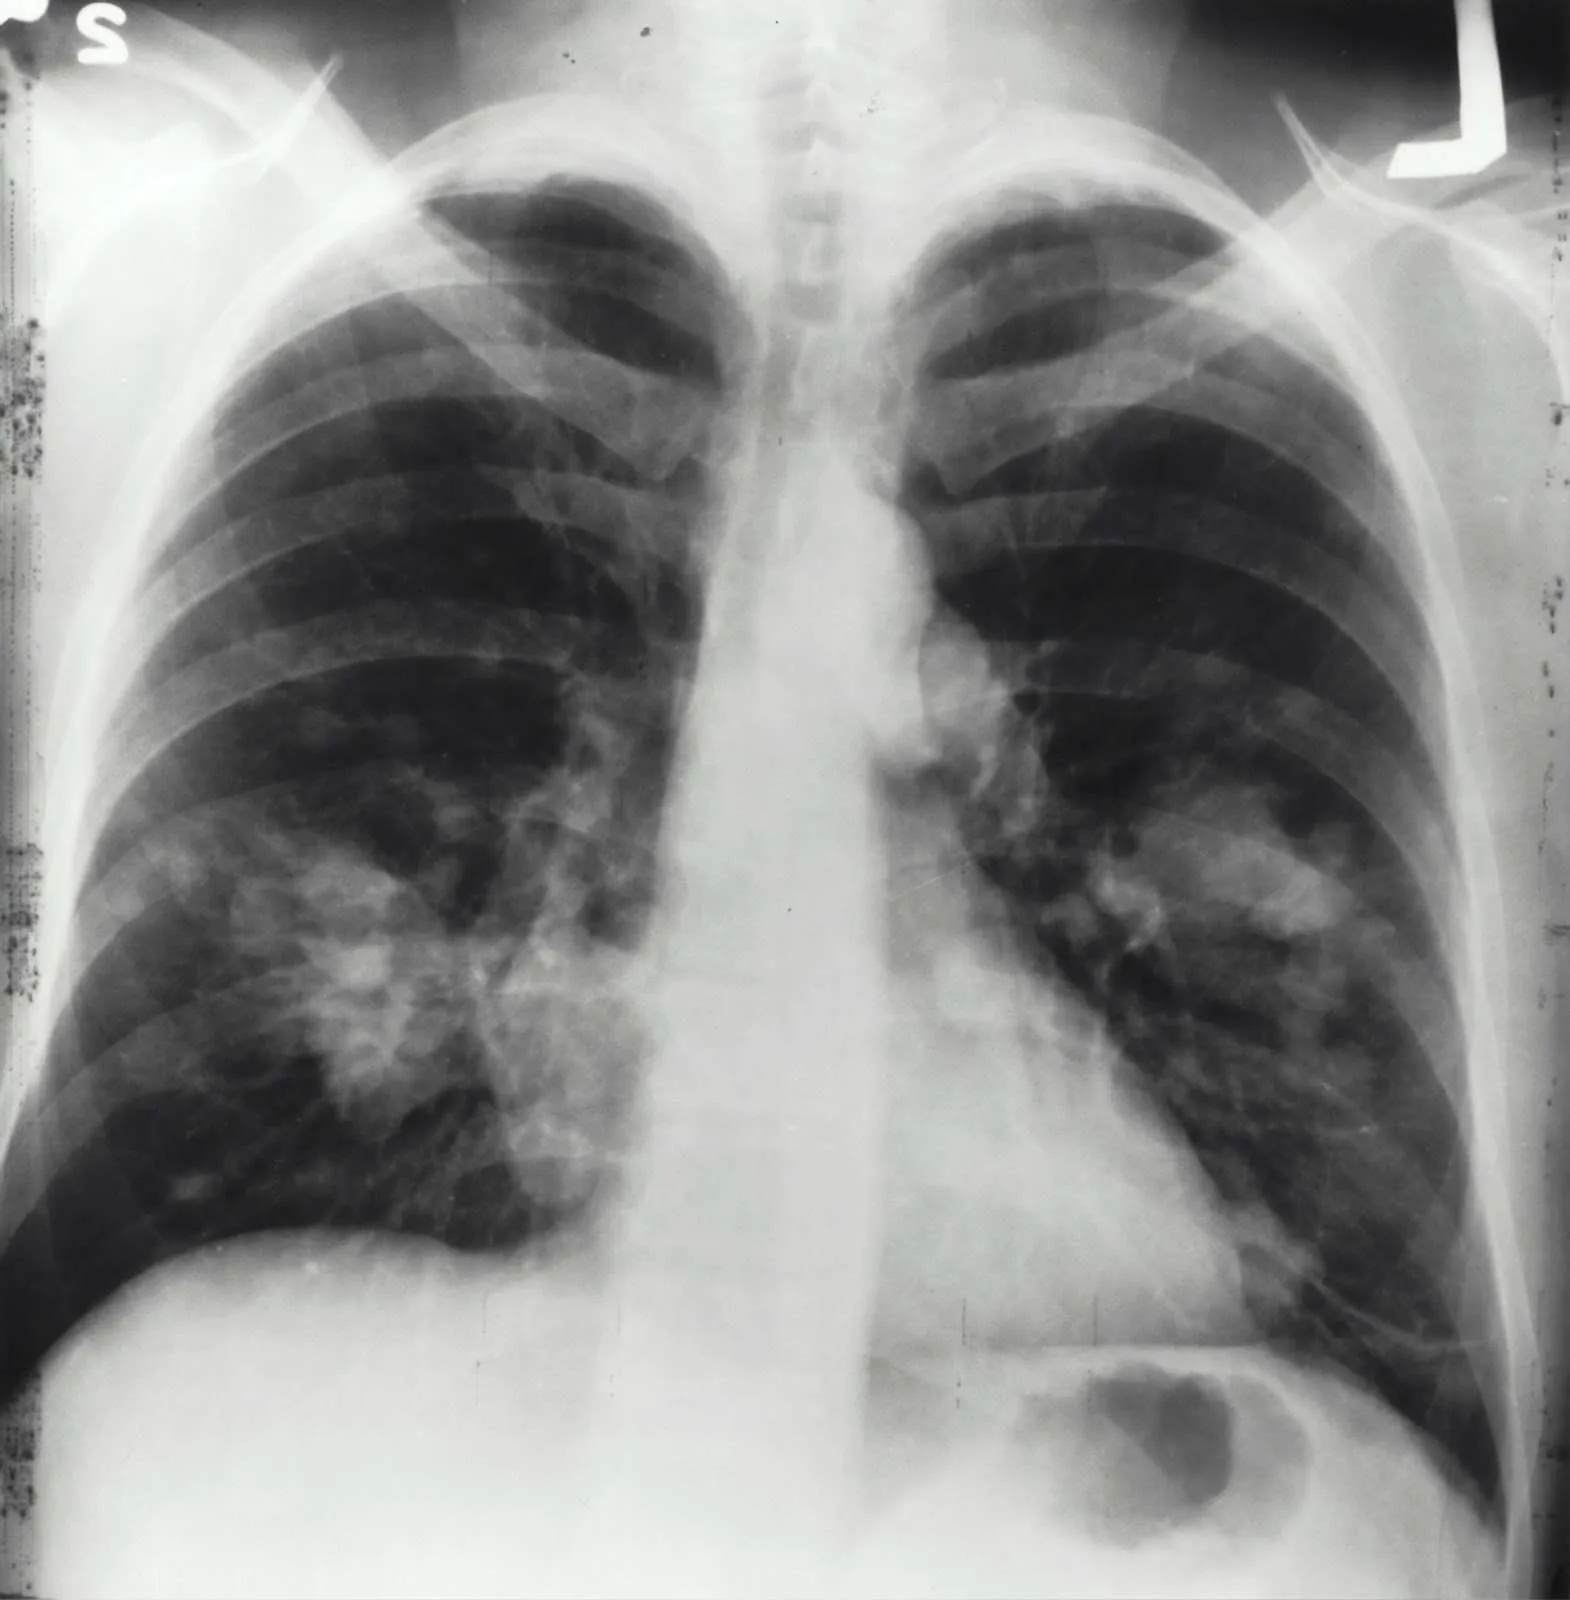

To confirm the blood panel results, genetic testing is used to pinpoint if you have specific gene mutations. Lastly, a pulmonary test is done to check if your lungs are working properly. Other tests also include liver function tests and imaging.